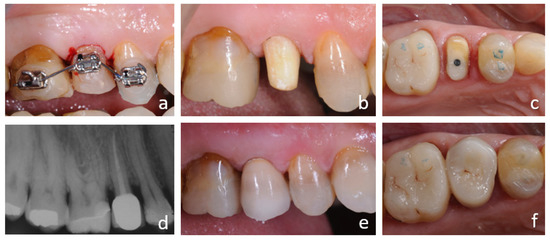

4.1. Orthodontic Extrusion

4.1.1. Advantages

4.1.2. Disadvantages

4.1.3. Complications

4.2. Surgical Extrusion

4.2.1. Advantages

4.2.2. Disadvantages

4.2.3. Complications

4.3. Combined Therapy